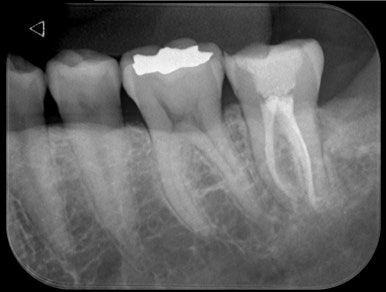

✅ 실제 치료 케이스 2: 우측 어금니 #47 C-shape canal

- 환자 증상: 어금니 통증, 씹기 어려움

- 진단: 크랙으로 인한 치수염, 신경치료 결정

🔬 MTA 실러 + GP cone 이용한 충전

| 전 | 후 |

→ C형 근관 특유의 얇은 통로까지 완벽하게 충전

→ 치료 후 통증 소실, 크라운 수복 완료